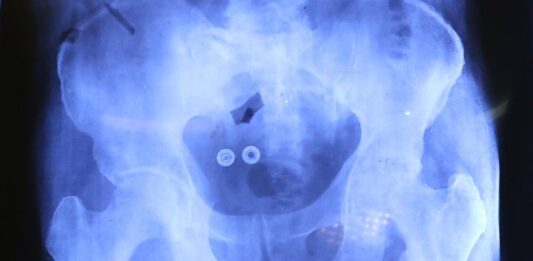

Inician cirugías de prótesis de cadera y rodilla para mayores de 60 años

En un esfuerzo conjunto, el Sistema Estatal para el Desarrollo Integral de la Familia (SEDIF), la Beneficencia Pública del Gobierno de México, IMSS-Bienestar y la Secretaría de Salud, iniciaron las cirugías de prótesis de cadera y rodilla para pacientes mayores de 60 años. Durante el fin de semana se realizaron las primeras tres intervenciones quirúrgicas … Sigue leyendo Inician cirugías de prótesis de cadera y rodilla para mayores de 60 años